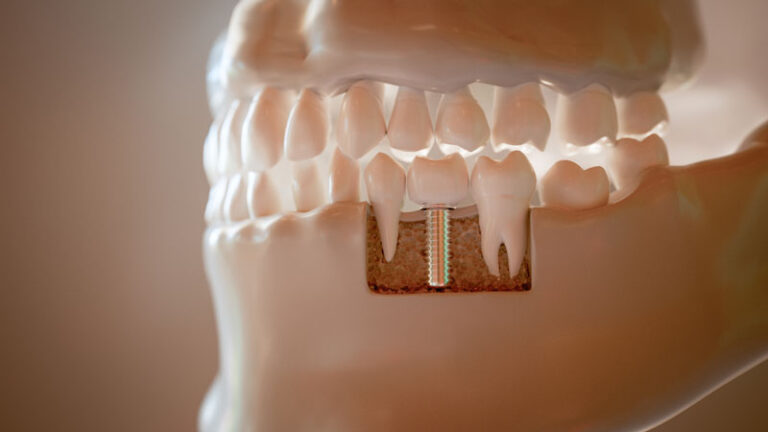

Dental implants are a standout choice among tooth replacement options due to their numerous advantages. Unlike dentures or bridges, which may not provide the same